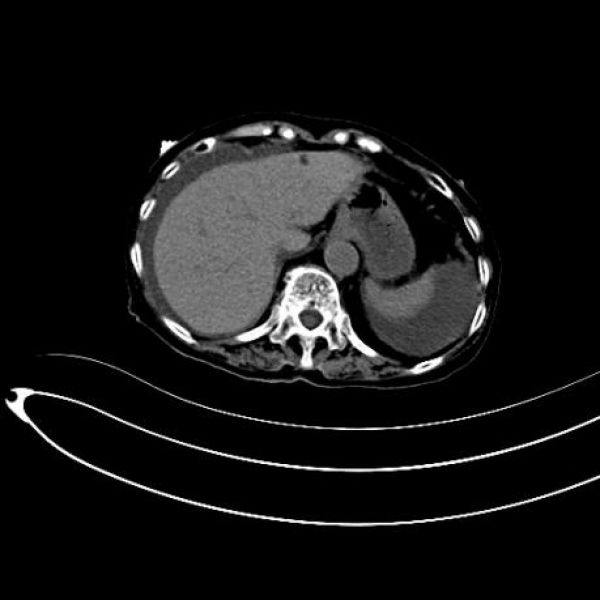

患者术前影像

该患者为什么不选择腔镜手术呢?因为患者胆囊穿孔致胆汁性腹膜炎,根据影响检查判断,患者腹腔明显大量胆汁性积液,通过腹腔镜是很难进行腹腔清洗的,患者术后快速康复的一个关键因素就是腹腔灌洗要充分,最大化减少术后腹腔胆汁残留。另外一个方面,患者急诊入院,呼吸情况不好,为减少气腹影响而快速完成手术,开腹也是最佳选择。作为一位成熟的外科医师,不能为了微创而微创,一定要综合分析,选择最有利于患者术后康复的治疗方案。